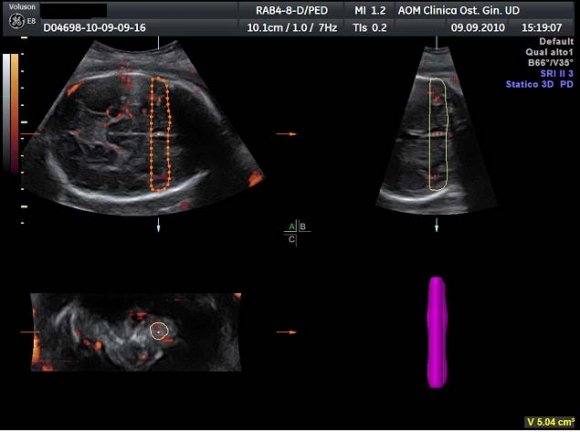

Moreover, power Doppler does not show aliasing effect and the colour map is independent of insonation angle. 15 The use of 3D-PD is particularly useful in the evaluation of fetal brain vessels because of their small caliber. 3D-PDA images of the fetal brain were acquired during fetal rest, using the same presets for each acquisition. The angle of acquisition was set at 35°, the pulsed repetition frequency (PRF) of the power Doppler at 0.9. We chose the biparietal plane including landmarks like the thalami, the third ventricle, the cavum septi pellucidi (CSP), the tentorial hiatus and a symmetrical display of the calvaria for recording power Doppler signals.

After displaying three simultaneous perpendicular planes on the monitor (axial, sagittal and coronal) the size of the region of interest (ROI) was adapted manually to created the two zones of the fetal brain to be analyzed (Fig. 1). These two ROI were defined by using anatomy landmarks to ensure a good reproducibility of this method among different operators. The first ROI is the Frontal Zone (zone 1), which has been obtained by tracing the contour of the anterior part of the fetal brain up to the perpendicular line crossing the anterior edge of the CSP (Fig. 2). The second ROI, Temporal Zone (zone 2), is defined by a rectangle reaching from both temporal bones with the width of CSP included (Fig. 3).

The volume of the investigated zones and the blood flow indexes were calculated using VOCALTM software. A rotation step for each contour plane was selected with a 30° angle chosen arbitrarily. This procedure of rotating the reference plane was done until a full rotation of 180° was achieved. The fetal brain volumes were calculated after all contour traced (6 steps). Eventually, the Vocal Histogram switch was activated for the automatic calculation of the 3D-PDA vascular indexes. Three vascular indexes were generated: vascularization index (VI) defined as the percentage of power Doppler data (coloured voxels) within the volume of interest; flow index (FI), the mean signal intensity (average colour value) of the power Doppler information; vascularization-flow index (VFI), a combination of both factors derived through their multiplication. 16 Inter-and intraobserver reproducibility was assessed with the intraclass correlation coefficient.